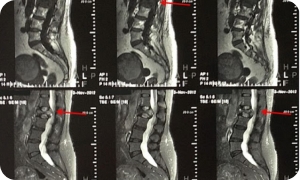

Магнитно-резонансная томография (МРТ)

Имеет клиническое значение для пациентов с переломами позвонков и компрессией спинного мозга, подозрением на наличие метастазов в головной мозг. Однако, многочисленные противопоказания к проведению МРТ требуют их первоочередного исключения у каждого, планируемого на МРТ пациента. Диагностические возможности МРТ в оценке костно-деструктивных изменений, в большинстве случаев, уступают КТ и ПЭТ/КТ.